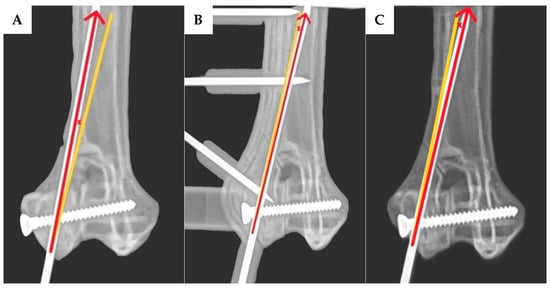

2.4. Assessment of the Transcondylar Screw and Epicondylar Pin Accuracy